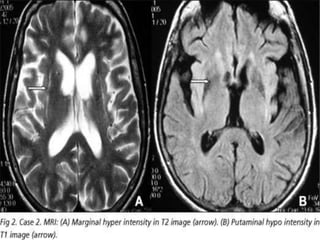

•IMAGINGFOR

PARKINSON’S DISEASE